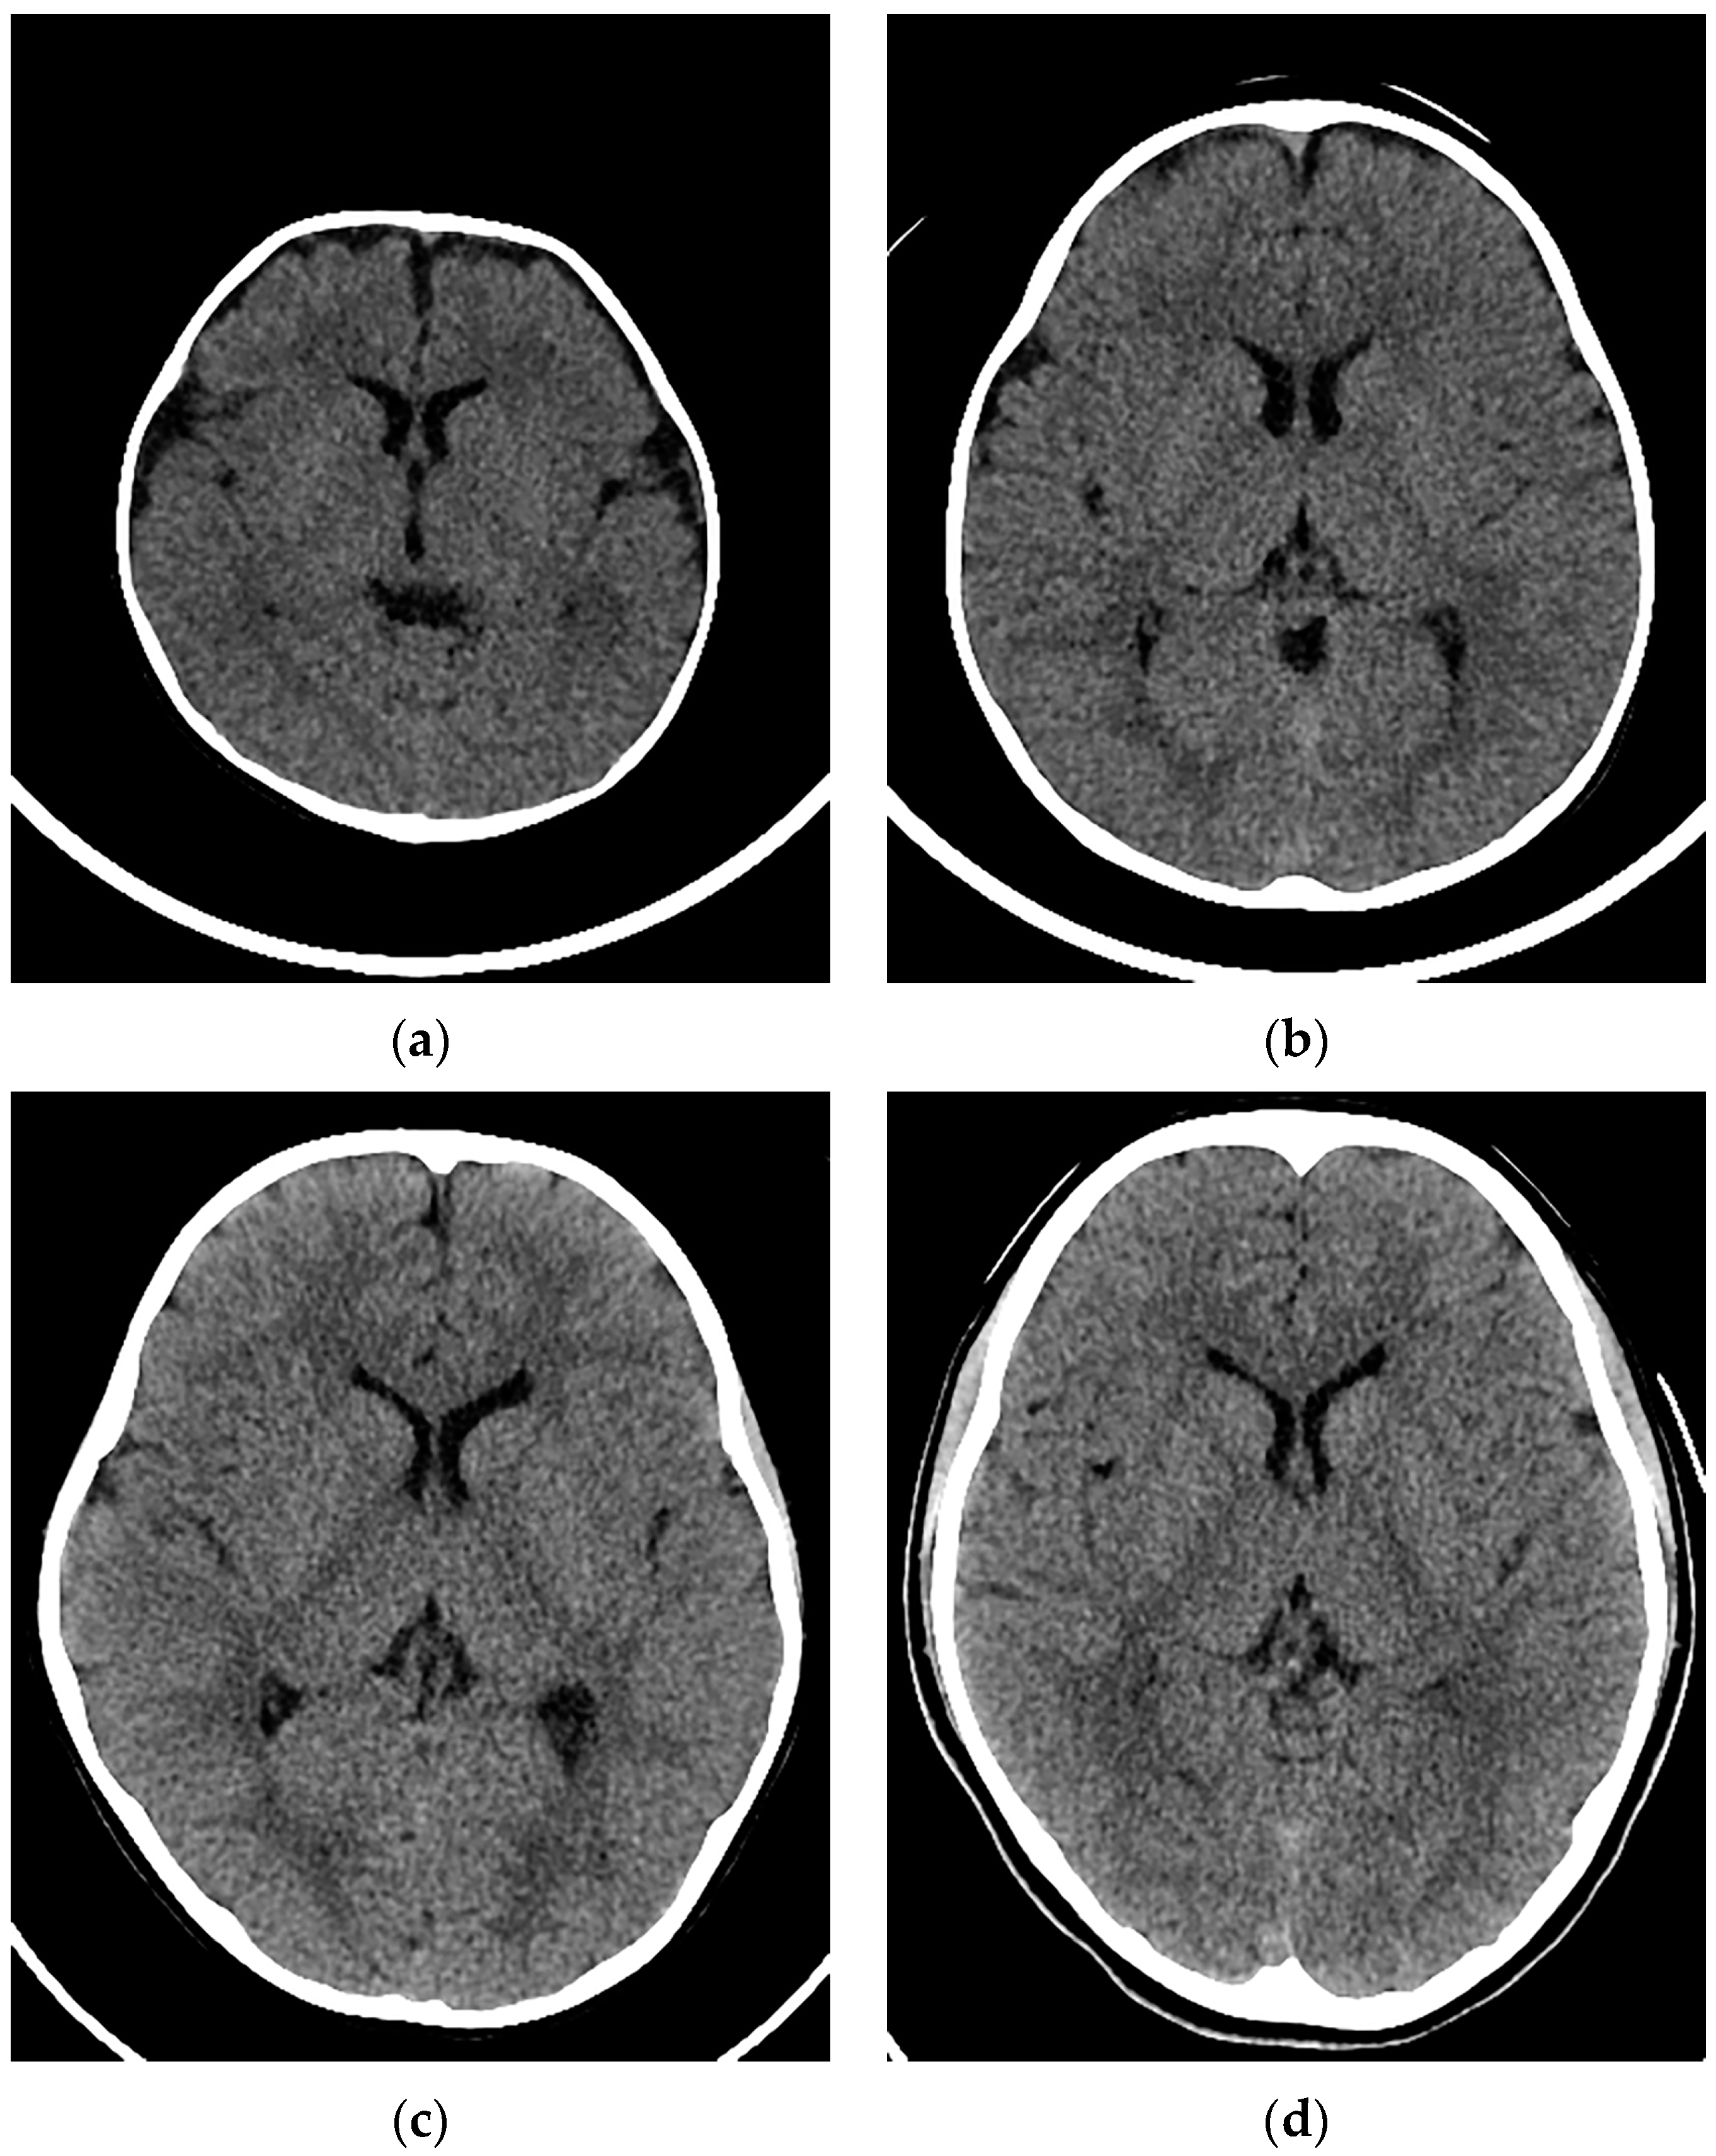

:1. Introduction

2.2. Imaging Procedures